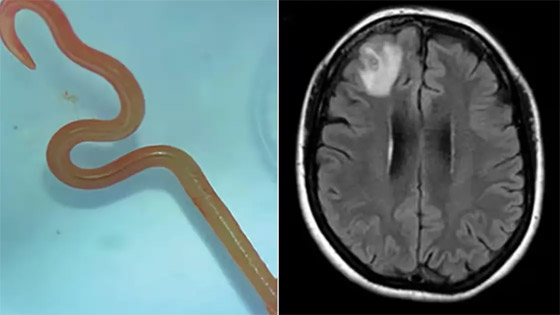

عقب استخراج الدودة أرسلت إلى أحد العلماء المتخصصين الذي أكد أنها دودة تتواجد في الثعابين. وقال تقرير الغارديان إنها أول حالة لاكتشاف هذه الطفيلي في البشر، موضحا أن المريضة تعيش قرب بحيرة تكثر فيها إحدى أنواع الثعابين. ورجح الأطباء والعلماء الذين درسوا حالتها أنها ربما وصلتها الدودة من خلال براز الثعابين في العشب.

من جهته، قال طبيب الأمراض المعدية في المستشفى، سانجايا سيناناياكي، إن هذا الأمر "يحدث مرة واحدة في حياتهم المهنية". وقال سيناناياكي إن المريضة تتعافى بشكل جيد، ولاتزال تخضع لرقابة طبية منتظمة، وأكد أن حالتها تسلط الضوء على خطر انتقال العدوى من الحيوانات إلى البشر.